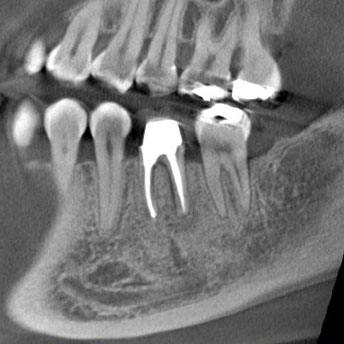

次の画像をご覧ください。これは、CTとレントゲンで同じ患部を撮影した画像です。

左の画像がCT、右がレントゲンで撮影したものです。

左の写真の赤丸で囲んだところは黒い影が映っています。これは「炎症」を示しています。一方、右の写真には黒い影はありません。つまり、レントゲンだけを使って診断すると、この炎症には気付かないということです。放置している間にこの炎症は悪化し、抜歯となってしまうかもしれません。

CTの鮮明な影像によって、正確な診断が可能になります。